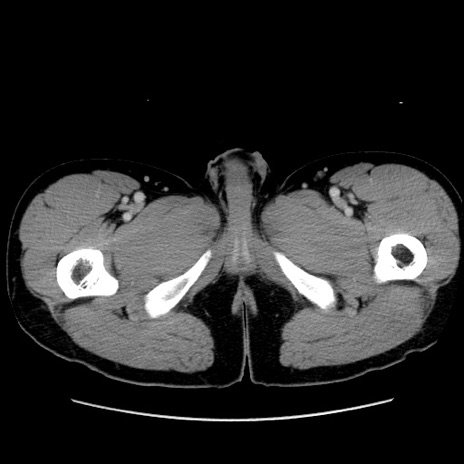

症例36(横断像)

【症例】20歳代 男性

【主訴】心窩部痛

【現病歴】今朝より上腹部痛あり。一旦軽快していたが再度出現したため救急要請。昨日夕に白身の魚を含む刺身を食べた。

【身体所見】BP 136/89mmHg、HR 74/min、BT 37.0℃、腹部:膨満、軟、心窩部に圧痛あり。反跳痛なし、筋性防御なし、腸雑音やや亢進あり。

【データ】WBC 17700、CRP 0.48